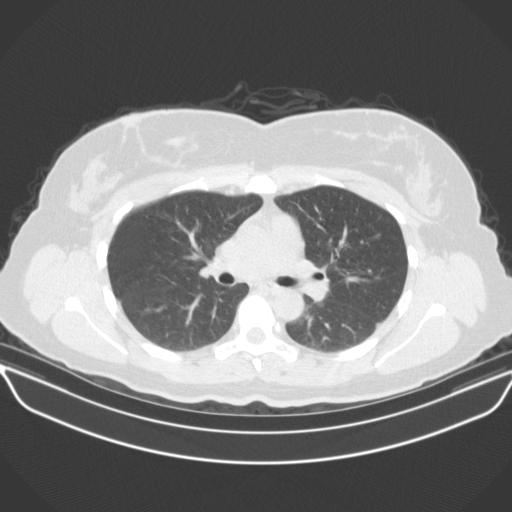

Targeted Slice 70 - Lung Window Analysis (Generated vs Real Venous)

0.763

Lung SSIM

85.0

Lung RMSE

36.7

Lung MAE

Average Lung Window Metrics Across All Slices (38 slices) - Generated vs Real Venous

0.768

Lung SSIM (Avg)

88.7

Lung RMSE (Avg)

36.8

Lung MAE (Avg)

Original NATIVE CT scan (input)

No window - Raw intensity values

Lung window (WL -600, WW 1500 β†’ Low βˆ’1350, High +150)